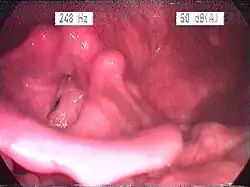

Im lupenlaryngoskopischen Bild fallen vor allem Hyperplasien der Schleimhäute überwiegend der posterioren (hinteren) Anteile des Kehlkopfes, des Ösophaguseingangs und der Rachenhinter- und Seitenwände auf. Typisch ist eine Hellfärbung und Fältelung der Schleimhäute, aufgrund der Verdickung entfaltet sich der Recessus piriformis weniger gut. Je nach Liegegewohnheiten kann durch überwiegend nächtlichen Reflux eine Bevorzugung einer Seite beobachtet werden. In neueren, experimentellen Studien konnten negative Einwirkungen des Reflux auf die Mikrostruktur der Larynxschleimhaut nachgewiesen werden. So führt der Magensaft zu einem verminderten Widerstand der Mucosabarriere mit der Folge leichteren Eindringens von Schadstoffen in tiefere Zellschichten.[1] Eine andere Untersuchung wies Veränderungen im Immunsystem der Schleimhaut (bei sogenannten Killerzellen) infolge eines Reflux nach.[2]

Standard ist nach wie vor das endoskopische Bild, auch wenn einzelne Studien gezeigt haben, dass die Befunde sehr variabel sein können und daher bei verschiedenen Untersuchern zu unterschiedlicher Interpretation führten. Als apparative Untersuchung zum direkten Nachweis eines Reflux zählt die 24h-pH-Metrie, wobei die klassischen Sonden mit Messpunkten im Magen und unteren Ösophagus nicht optimal sind, da nur ein Messpunkt im Hypopharynx den Reflux in der Zielregion erfassen kann. Daher sind spezielle Messsonden mit entsprechender Konfiguration besser geeignet. Zur allgemeinen Abklärung einer Ursache (z. B. Hiatushernie) ist eine Magenspiegelung erforderlich (siehe auch Refluxösophagitis). Auch bereits ein nicht-obstruktives Schnarchen kann refluxfördernd sein, da durch die Verlegung der Atemwege ein erheblicher Druckgradient vom Magen zum Thorax-/Halsraum entsteht.[3][4][5] Der thorakale Unterdruck bei (frustraner) Inspiration steigt erheblich an, der Magensaft wird nach oben gesaugt. Daher ist ggf. auch eine Polysomnographie im Schlaflabor, optimalerweise mit Somnoendoskopie, erforderlich.